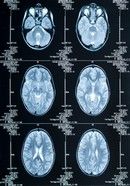

Radioterapia afecteaza creierul

Radioterapia utilizata pentru tratarea tumorilor de la nivelul creierului poate sa conduca la declin mental, titreaza BBC News.

Studiul realizat pe un esantion de 65 de persoane si publicat in revista "The Lancet Neurology" arata ca la 12 ani de la tratament, pacientii care au apelat la el sunt mult mai predispusi la a intampina probleme cu memoria. De asemenea, cercetatorii le propun medicilor sa nu utilizeze pe cat posibil radioterapia.Persoanele care au participat la studiu avea gliom cerebral de grad redus, una dintre cele mai intalnite tumori care se dezvolta la nivelul creierului. In acest caz, radioterapia este utilizata dupa interventia chirurgicala de extirpare a tumorii, insa expertii se intreaba daca nu ar fi mai sigur ca tratamentul sa fie utilizat doar in cazul unei recidive.

"Intotdeauna depinde de pacientu, insa daca este posibila o amanare a radioterapiei poate ca ar fi optiunea cea mai sigura", afirma dr. Linda Douw din cadrul departamentului de neurologie de la centrul medical al Universitatii VU din Amsterdam care adauga ca vor continua cercetarile si in privinta altor terapii, cum ar fi chimioterapia.